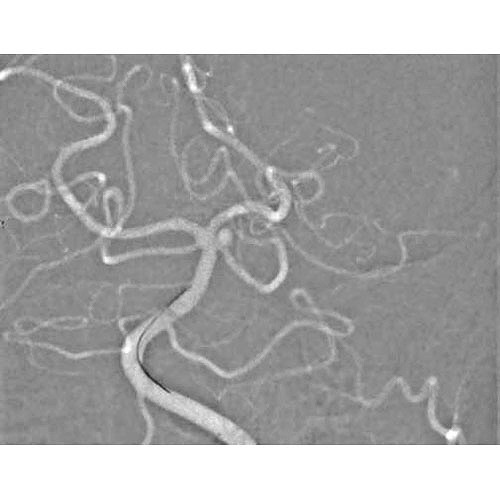

The slice dimensions of the reconstructed imag-es were 512 512 pixels with approximately 440. All DSA images were categorized as with or without misregis-tration artifacts by two authors DU.

8 Mar 2021 Siemens Artis Zee BA by msolutions posted in. System Artis Zee BA Twin Siemens Healthcare with a 5-second rotation program. Subsequently contrast-enhanced C-arm cone beam CT images were acquired using a commercially available flat-panel angiography system Artis Zee BA Twin Siemens Healthcare with a 5-second rotation program.

Three-dimensional slice data in DICOM format reconstructed from the clinical images acquired by digital subtraction angiography AXIOM Artis dBA Twin Artis Q BA Twin Artis zee BA or Artis zeego Siemens Healthcare GmbH Forchheim Germany were used in all the cases except that of an anterior communicating artery Acom IA. Which were acquired by using Artis Zee BA Twin equipment Siemens Healthineers. Eight patients with 8 HCC lesions less than 30 cm in diameter were entried.

Artis zee i のFull-16bitイメージングチェーンがもたらすハイクオリティな3Dイメージは信頼性の高い術中支援画像として高度なインターベンションを強力にサポート臨床領域に応じた多彩なガイダンス機能との組み合わせで診断治療. All DSA procedures were performed with a biplane flat-panel angiography system Artis zee BA Twin.